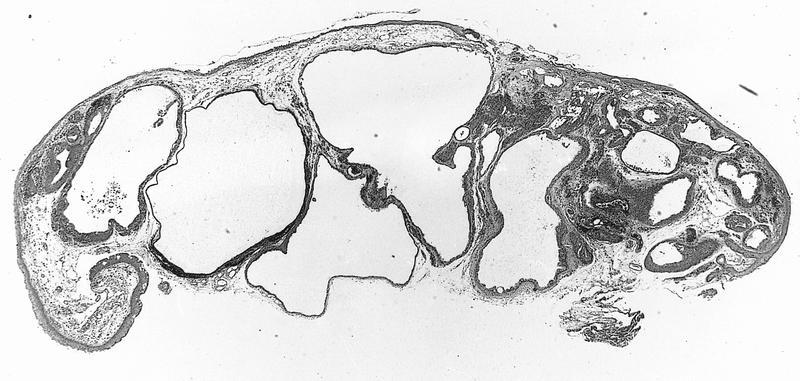

- Subepithelial (9%):

- Nevus cells only in subepithelial connective tissue, no pigment, bland nuclei

- May have clear cytoplasm due to lipid and central round nucleus (balloon cell nevus)

Cystic compound nevus:

Balloon cell: